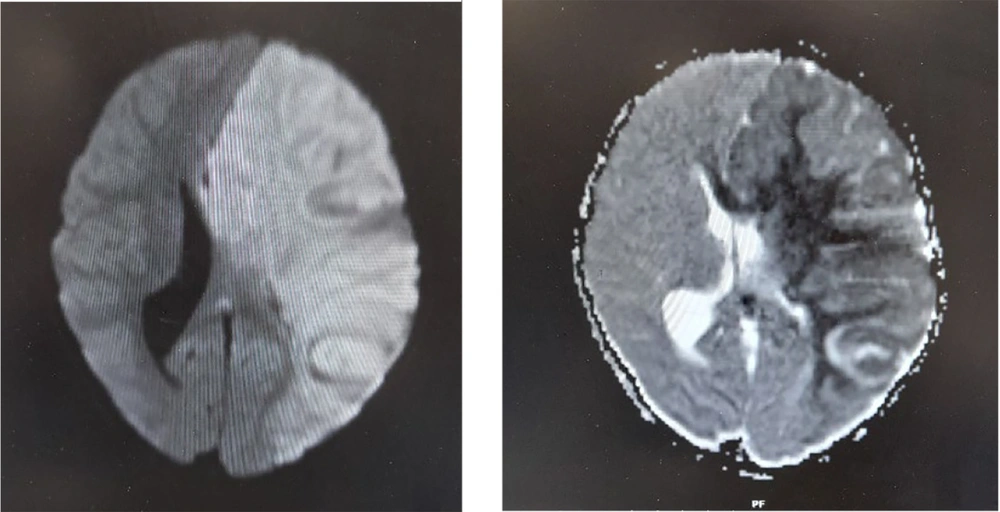

Three days after successful extubation, the patient demonstrated abnormalities in limb tone and force, as well as anisocoria. Brain MRI showed severe generalized edema, ischemia, and herniation (Figure 2). Antiepileptic drugs were started due to brain damage. Following a severe increase in intracerebral pressure, a craniotomy was performed, and supportive treatment continued. A brain biopsy showed inflammation and bleeding. MRA (Magnetic Resonance Angiography) showed a filling defect in the right vertebral artery. Post-craniotomy MRI reported mild herniation through the craniotomy site. An abnormal T2/FLAIR high signal was noted in the left cerebral hemisphere, left basal ganglia, and left thalamus as a sequel of infarction. Hemorrhagic changes in the left frontal lobe were seen, with multiple areas of gyral T1-high signal mostly suggestive of cortical laminar necrosis (Figure 3). There were no changes in favor of HSV in the MRI. Post-craniotomy CT scan showed parenchymal edema and hemorrhagic changes in the left frontal lobe, with abnormal hyper-dense foci noted in the genu and splenium of the corpus callosum and left caudate nucleus (Figure 4). The patient was diagnosed with cerebral stroke. CSF PCR for HSV from the brain biopsy, serum HLA B51, IgA, IgG, IgM, IgE, ANA, lupus anticoagulant, TG, cholesterol, HDL, LDL, pANCA, cANCA, anti-coagulant IgG and IgM, anti-cardiolipin IgG and IgM, protein C, protein S, anti-thrombin 3, F-ANA, anti-B2 glycoprotein, anti-DNase, IL-6, and anti-Smith were performed (Table 1).